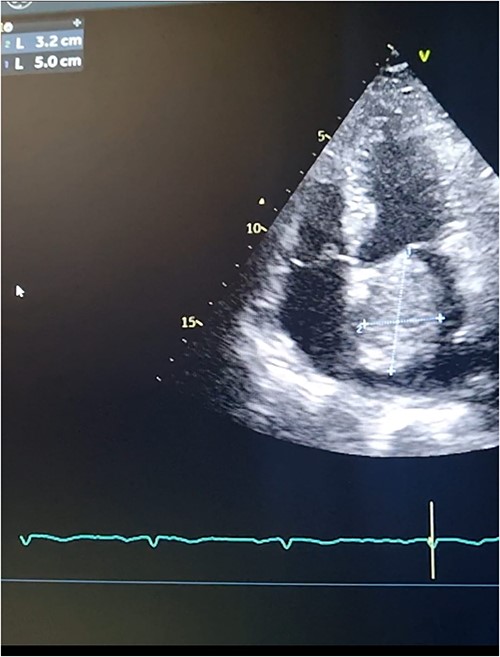

Meanwhile, transthoracic echocardiography was done to investigate the cause of loud S1 and fingers clubbing. The Echocardiography showed a large heterogeneous mass attached to the fossa ovalis in the left atrium. (Figs 1A, B and 2). This was followed by obtaining a computed tomography (CT) scan of the chest to investigate for other causes of hemoptysis. The CT scan showed no other identifiable etiology precipitating hemoptysis. Thus, it was determined that elevated pressure in the pulmonary vessels secondary to obstruction in the mitral valve blood flow caused hemoptysis in the presented case. A preoperative diagnostic coronary angiography showed normal coronaries with no evidence of stenosis.

Transthoracic echocardiography. (A) Echocardiogram parasternal long-axis view (PLAX) view showing large homogenous mobile mass in LA. (B) Echocardiogram parasternal short-axis view (PSAX) view showing Left atrial mass protrusion through the Mitral valve during diastole.

Transthoracic echocardiography. 2D measurements of the LA mass measuring 5 cm * 3.2 cm.